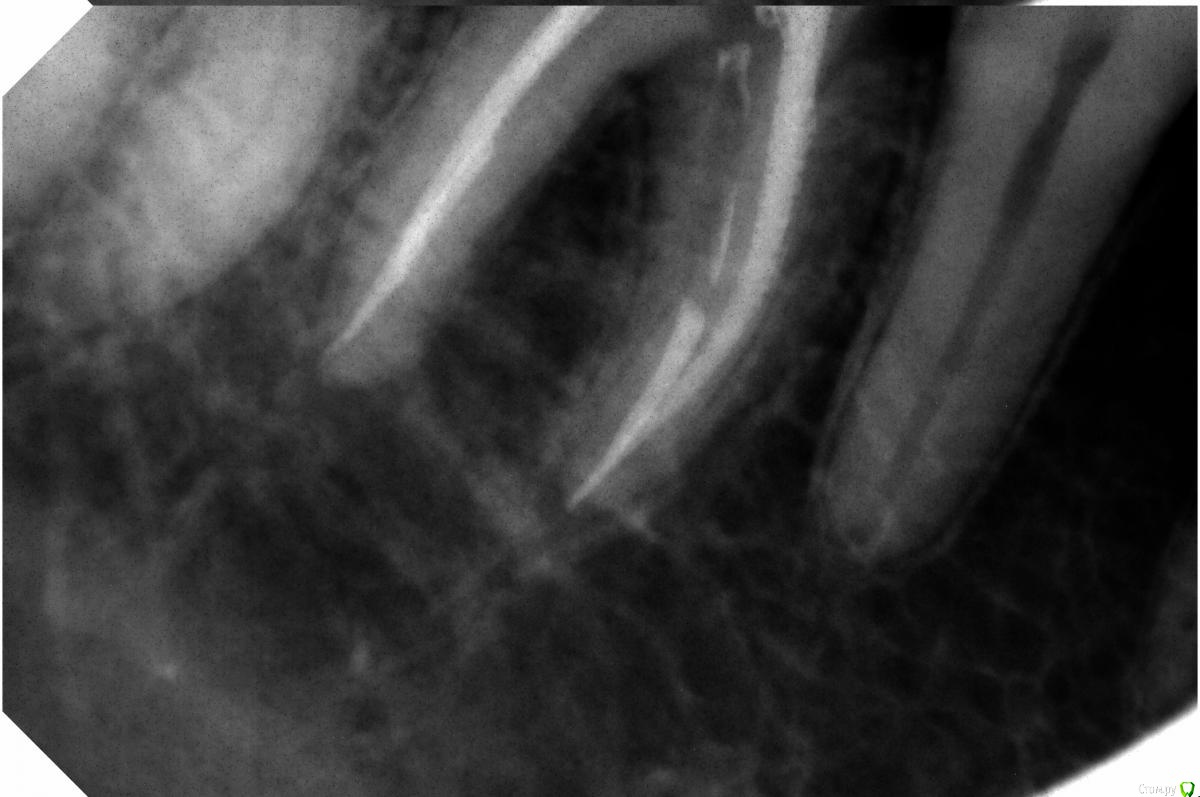

kot495 Опубликовано 8 сентября, 2016 Автор Поделиться Опубликовано 8 сентября, 2016 Привет! Спасибо за ответы. Мне предлагают еще такой вариант: каким-то образом разделить зуб на 2 части там где трещина, удалить патологически измененную ткань, и сделать на штифтах. Как считаете, возможно ли это в моем случае, и каков будет прогноз? Или обоснуйте удаление или другой вариант. Прилагаю снимки. Ссылка на комментарий

Bier Опубликовано 8 сентября, 2016 Поделиться Опубликовано 8 сентября, 2016 коронковой части зуба не видно. Не занимайтесь ерундой. Удалите зуб, если он подлежит удалению 3 Ссылка на комментарий